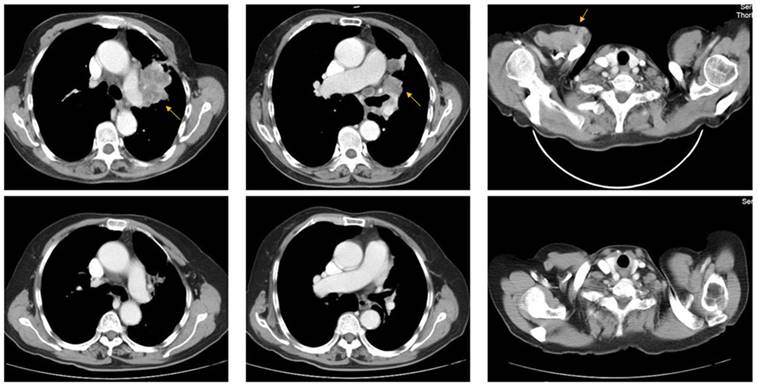

A 73-year-old woman (patient case 025) was diagnosed with lung adenocarcinoma with bilateral intrapulmonary, hilar lymph node, mediastinal lymph node, and subcutaneous metastasis (cT3N2M1b IV; AJCC 7th Edition). Expanded molecular testing revealed KRAS exon3 Q61K mutation. Then she was included in the clinical trial (NCT02477826) and received 4 cycles of nivolumab plus chemotherapy (pemetrexed and carboplatin) as first-line treatment from June 8, 2017 to Aug 10, 2017. After two cycles of treatment, the patient was with rapid dramatic clinical improvement, later confirmed as an excellent radiographic partial response by computed tomography scanning (Fig 3). After then, she received 5 cycles of nivolumab plus pemetrexed as maintenance therapy from Sep 1, 2017 to Nov 24, 2017. The PFS was 6.2 months, significantly better than the median PFS of 1.5 months in the KRAS-mutant cohort.

Fig 3

Representative pre- (upper row) and post-treatment (lower row) computed tomography (CT) images in a 73-year-old woman (patient case 025) diagnosed with advanced lung adenocarcinoma with KRAS exon3 Q61K mutation. After 2 cycles of treatment (Nivolumab + pemetrexed + carboplatin), metastatic lesions (yellow arrow) became markedly reduced compared with those in pre-treatment CT images.